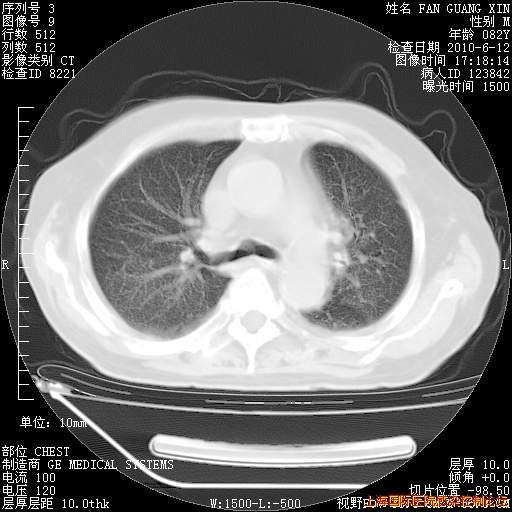

补发6月12日肺部CT肺窗

6月12日肺窗